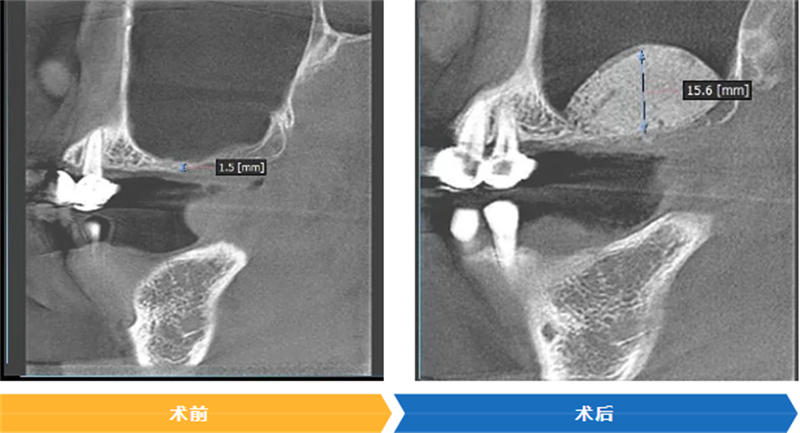

CBCT檢查顯示,藍女士右上后牙區牙槽骨垂直高度不足2mm,臨床診斷為牙列缺失伴隨垂直向頜骨缺損,不符合常規種植條件。為了幫助藍女士實現重新舒適進食、提升生活品質的目標,口腔科啟動多學科聯合會診,最終確定采用Sticky Bone技術實施引導骨再生手術,為后續的種植修復創造基礎。

隨后,醫師精準將這種“生物粘合劑”植入右側上頜竇底的骨缺損區域。術后復查顯示,藍女士該區域牙槽骨量顯著增加,為種植體植入預留了充足條件。“沒想到這么順利就能解決問題,感覺像獲得了新生!”藍女士難掩激動。